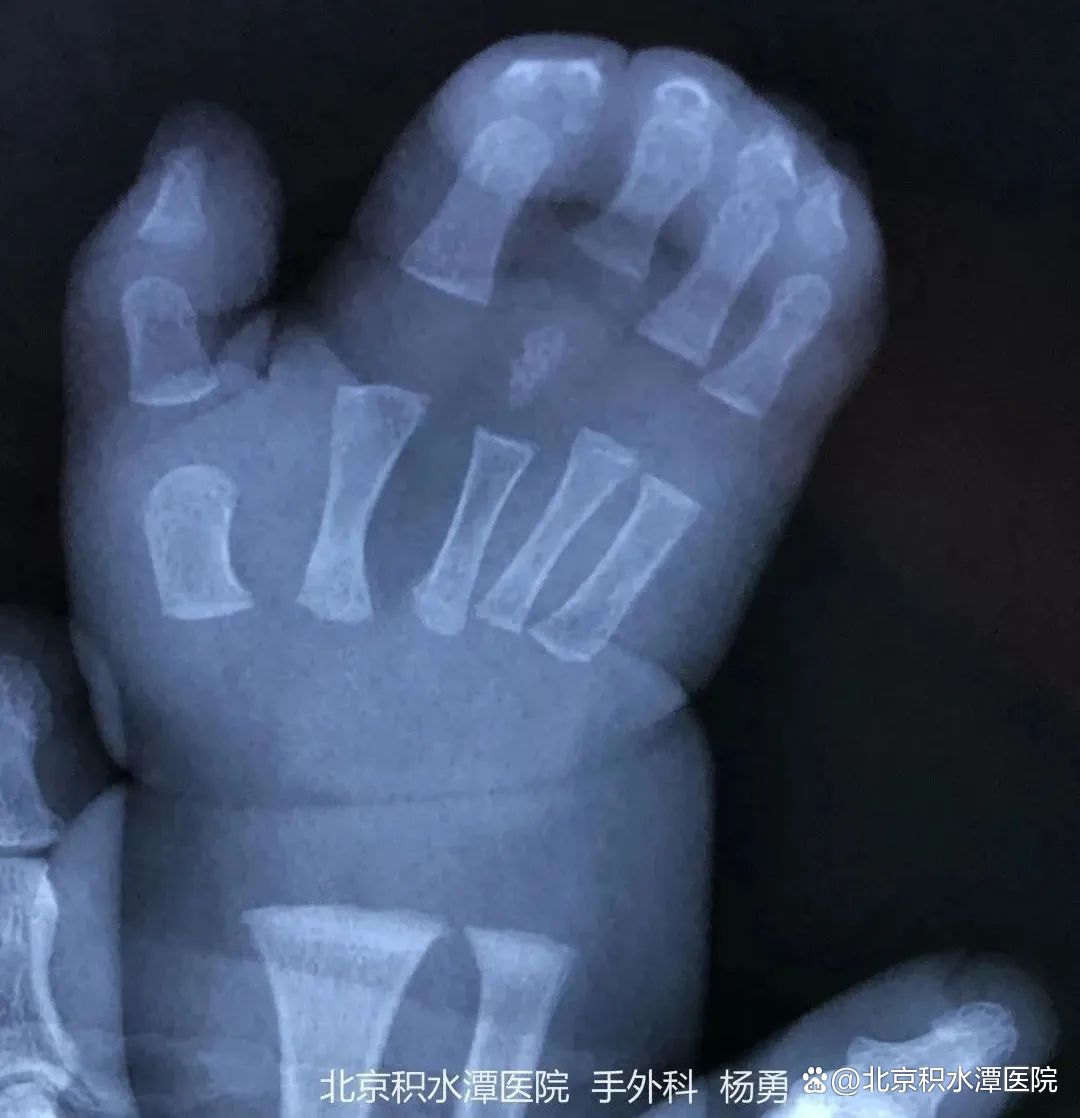

除了人们常说的”六指“,也就是拇指畸形,临床上还有一种小儿手部常见的先天畸形——并指畸形。并指畸形是一种出生后即可发现的手部畸形,在新生儿中的发病率为0.2‰~0.3‰,男孩发生率略高于女孩,手部并指多于足部并趾。

图|我院手外科接诊的手部畸形患儿

很多家长因为孩子的并指畸形而感到束手无策,今天,手外科主任医师杨勇全面详解先天性并指畸形,为家长排忧解难。